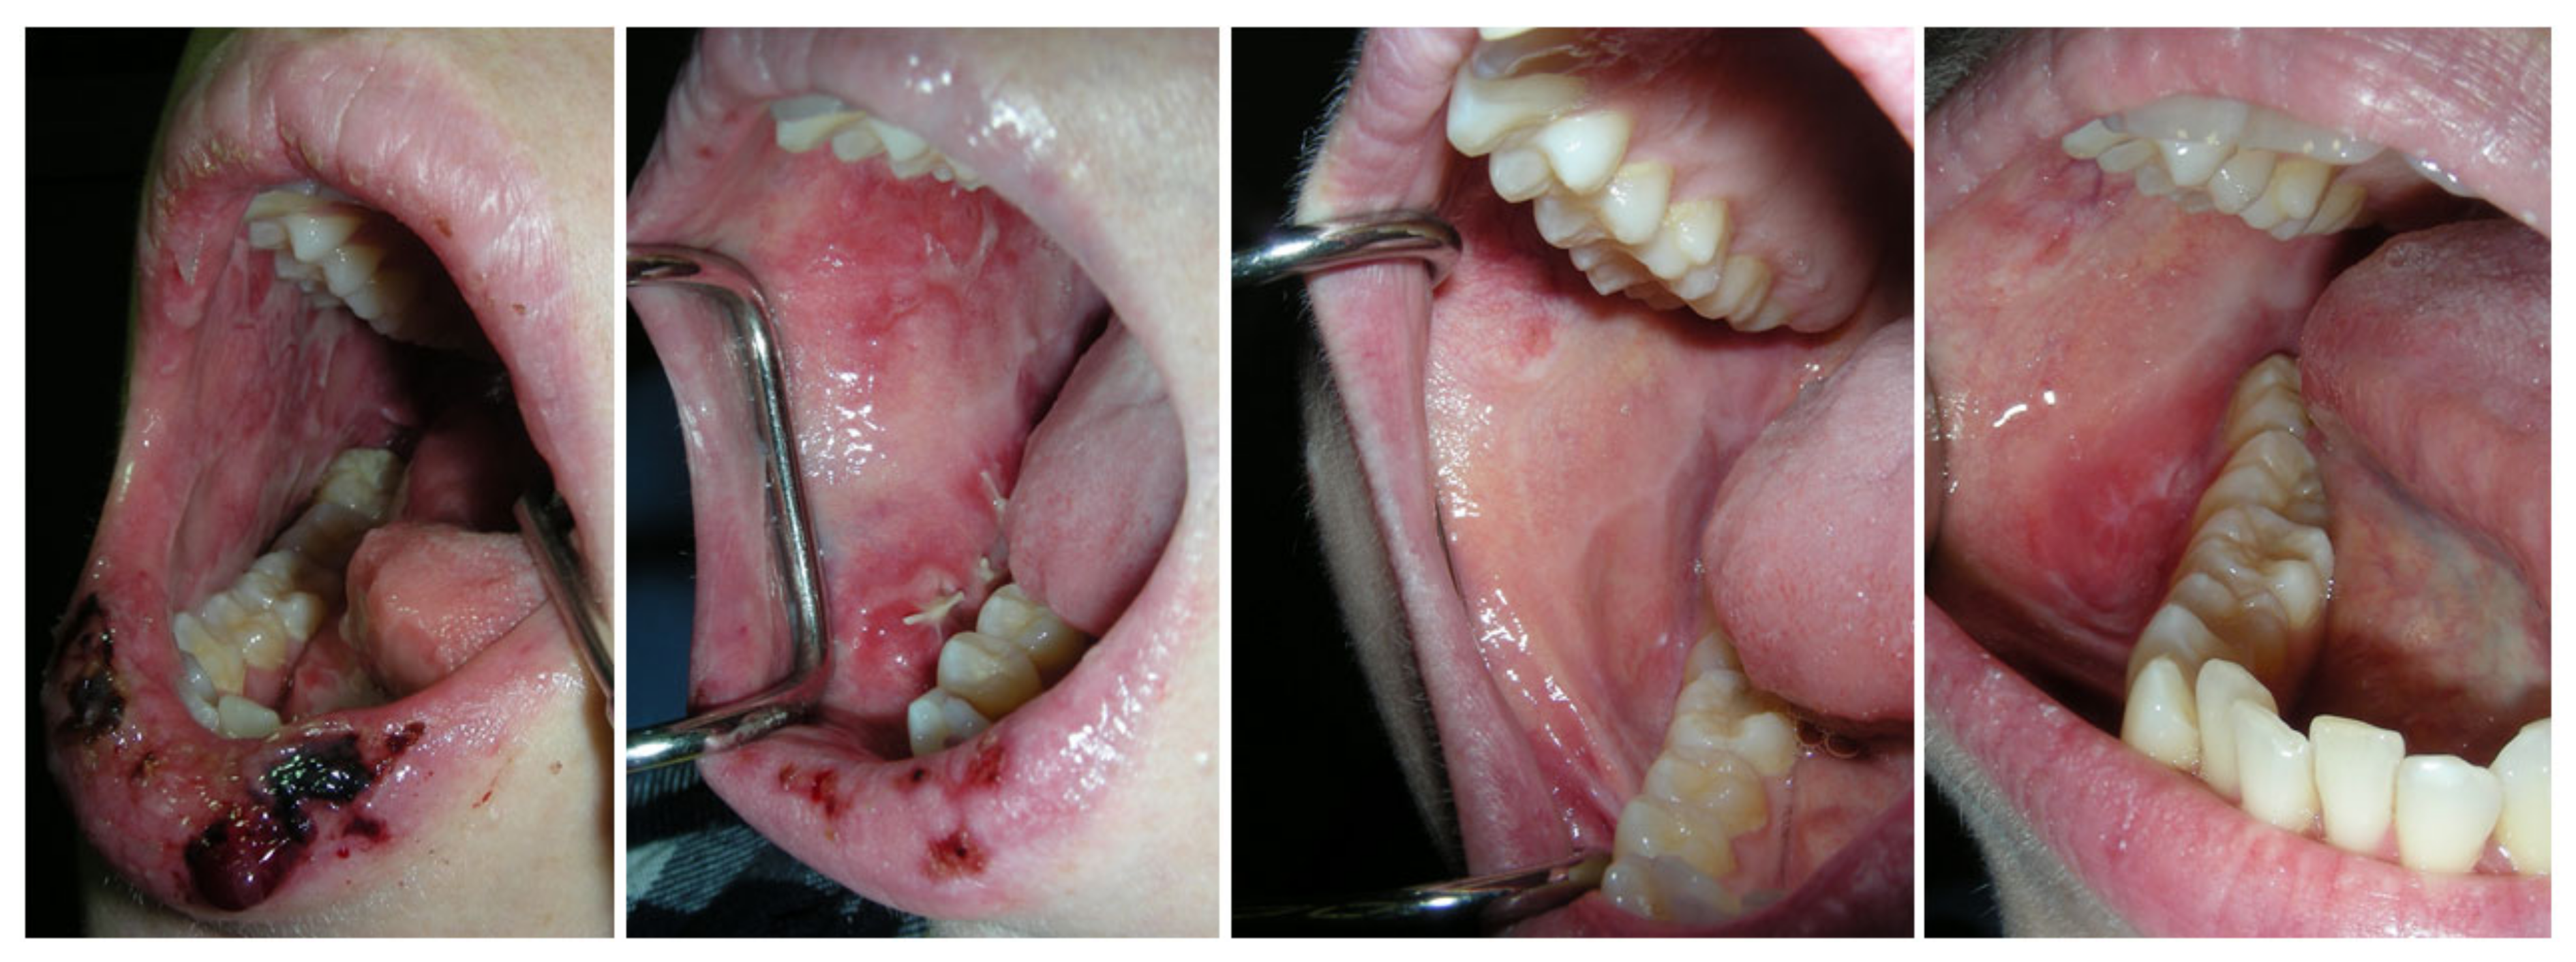

| Type of lesions | |||||||||||||

| Lichenoid | x | x | x | x | x | x | x | x | x | x | |||

| Erythema | x | x | x | x | x | x | x | x | x | ||||

| Ulcer | x | x | x | x | x | x | x | x | |||||

| Other | Lip crusts | Bleeding, Pigmentation | Thinning of the mucosa | Thinning of the mucosa | Thinning of the mucosa | Mucoid saliva, thin white plaque | Mucoid saliva | ||||||

| Lips | x | x | x | x | x | ||||||||

| Buccal mucosa | x | x | x | x | x | x | x | x | x | ||||

| Labial mucosa | x | x | x | x | x | x | x | ||||||

| Tongue Dorsum | x | x | x | x | |||||||||

| Tongue Sides | x | x | x | x | |||||||||

| Palate–Hard | x | x | x | x | x | ||||||||

| Palate–Soft | x | ||||||||||||

| Floor of Mouth | x | ||||||||||||

| Gingival tissue | x | x | x | x | x | ||||||||